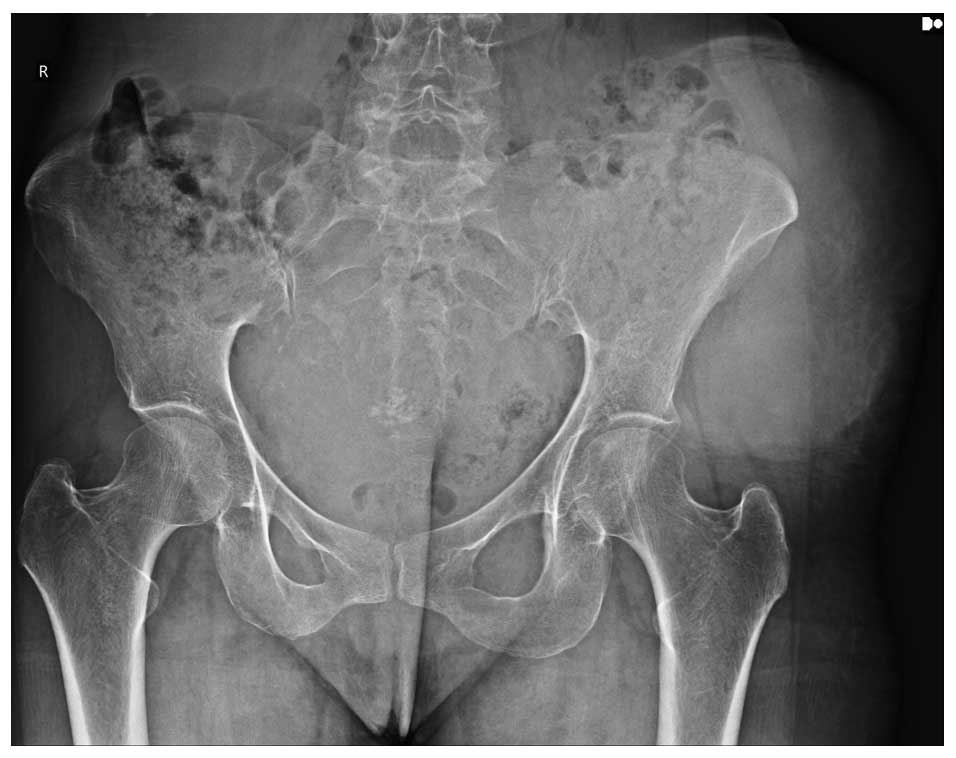

Ameliyat Öncesi: Röntgende yumuşak doku gölgesi görülmekte.